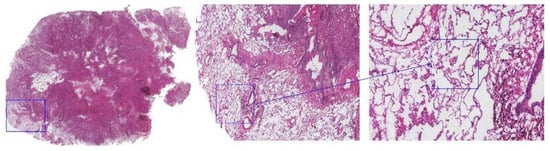

Figure 1.

Micropapillary clusters were observed in the air space of the lung beyond the margin of the main tumor under a digital biopsy scanner and were recorded as STAS-positive. The three panels represent progressively increasing magnifications—1× (left), 100× (middle), and 400× (right)—acquired using a digital scanner. The blue square in the low-power image indicates the region selected for high-power observation. The magnified image was captured at 400× total magnification (objective lens 40×, eyepiece 10×).